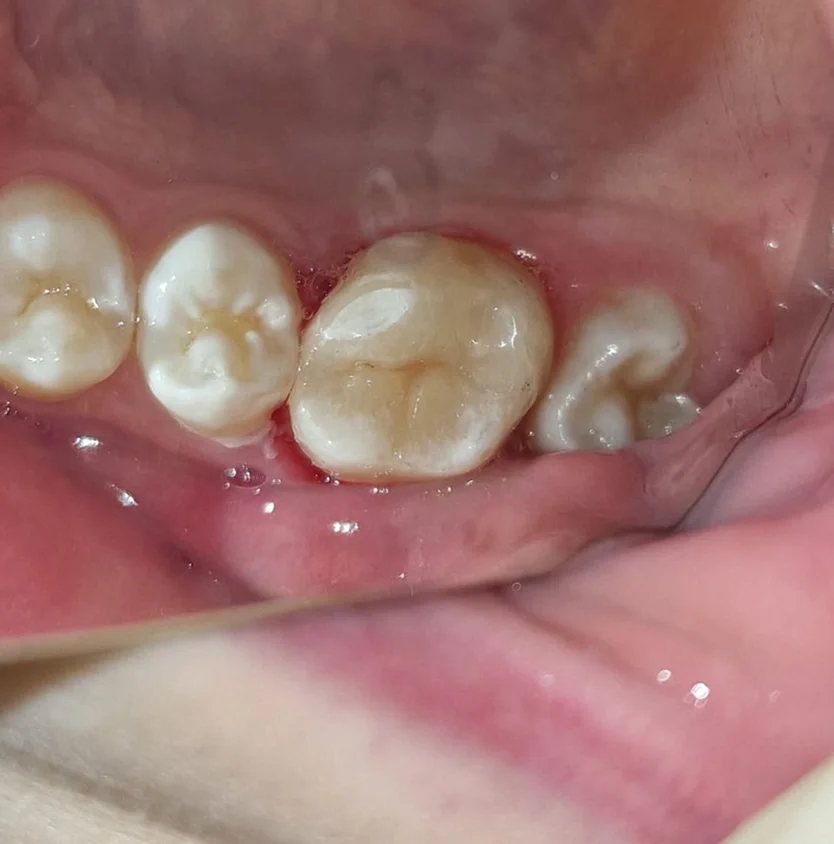

Зуб в зубе (dens invaginatus): диагностика и тактика лечения

Механизм формирования инвагинации. Клинические проявления и рентгенологическая картина. Риски осложнений и алгоритм принятия решения о лечении. Особенности эндодонтического лечения при разных степенях инвагинации.